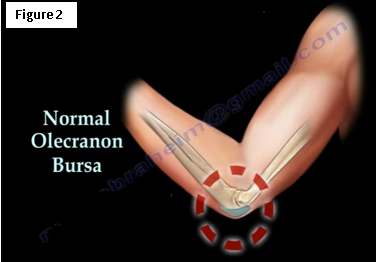

The normal olecranon bursa provides protection and decreases friction to the elbow joint and contains a little fluid (Figure 2).